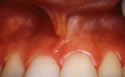

beforeThe muscles of the cheeks and lips are attached to the gums and tissue of the mouth by a piece of soft tissue called a frenum. Sometimes a frenum can be attached too high on the gums causing either recession or spaces between teeth.

afterA Frenectomy is a simple procedure where either part or all of the frenum in question is removed in order to return a healthy balance to the mouth.